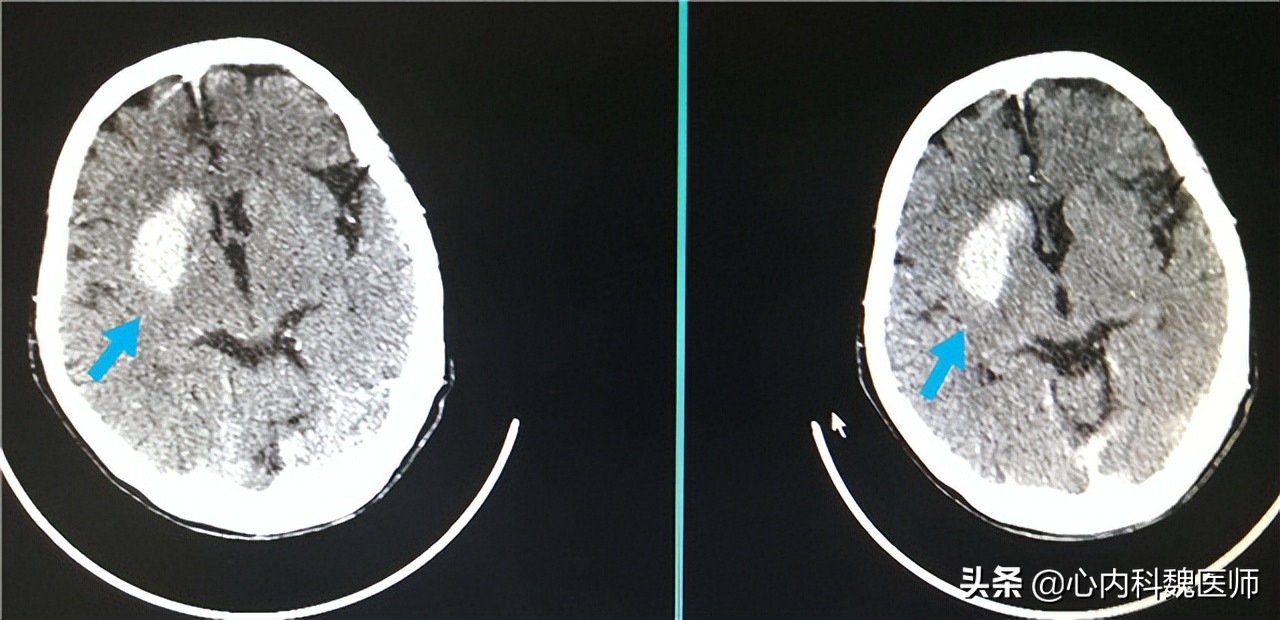

急救人员来到后发现王叔已经失去意识,出现大小便*禁失**的现象,随后立马给予王叔湿化氧气,测量生命体征。通过脑部CT发现梗死灶,确定王叔发生了脑梗,立马给王叔进行溶栓治疗,通过颈动脉造影发现许多斑块,通过连续监测颈动脉斑块确定斑块无闭塞风险,最终王叔抢救成功。